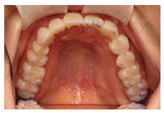

12、24、34、44牙缺失,12牙缺失牙间隙无,13牙与11牙建立邻接,24、34、44牙缺失牙间隙减少。咬合检查:上颌牙中线与面中线一致,下切牙中线右偏约1.5mm,11、13牙对刃,前牙部分开

,21、22、23、43牙与对侧牙无咬合接触,后牙有咬合,磨牙中性关系。余检查同术前(图8,图9,图10,图11)。